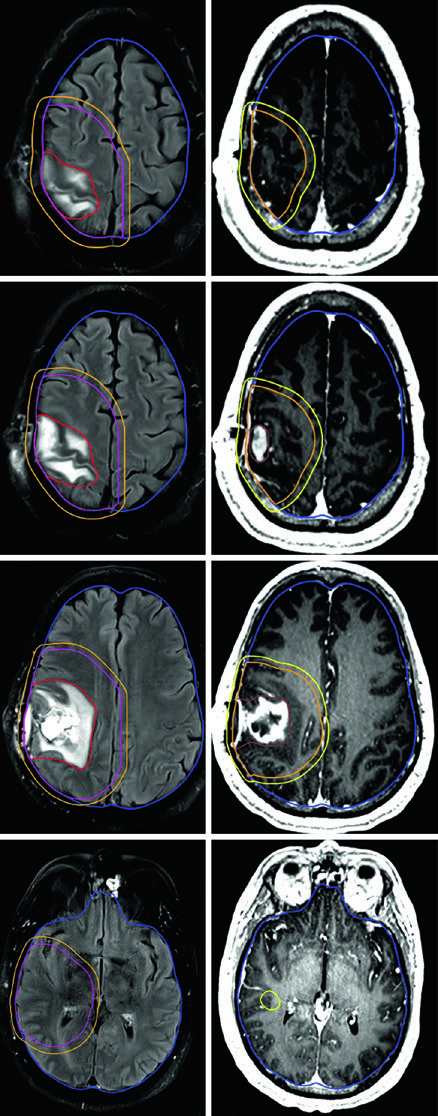

Pacientes idosos ou com performance status comprometido representam um desafio particular. O esquema de 40 Gy em 15 frações funciona bem quando há pouco volume FLAIR fora do tumor captante — o GTV inclui cavidade de ressecção, tumor residual e nódulos satélites na T1 pós-contraste, com expansão de CTV de apenas 1,0 cm e restrição anatômica ao tentório.

Para situações ainda mais agressivas em termos de prognóstico, o regime ultra-hipofracionado de 25 Gy em 5 frações é uma opção, com margens de 0,5 cm do GTV para o CTV. Um exemplo típico é o glioblastoma cerebelar — a cóclea e o tronco encefálico ficam visíveis e servem como referência direta na dosimetria.

Já o gliossarcoma segue paradigma semelhante ao do glioblastoma. Dois volumes sequenciais costumam ser empregados — o primeiro baseado no FLAIR (46 Gy) e o segundo na T1 pós-contraste (60 Gy), com expansões de CTV de 1,5 cm anatomicamente restritas.

Alguns erros recorrentes no planejamento de tumores malignos do SNC merecem destaque. O mais comum é aplicar expansões isotrópicas sem respeitar as barreiras anatômicas. O CTV de um glioblastoma frontal não deve cruzar a linha média — a menos que o joelho do corpo caloso esteja em risco, caso em que essa estrutura deve ser explicitamente incluída. Outro erro é ignorar a diferença entre as sequências de RM: o GTV1 deve ser baseado no FLAIR (edema perilesional), enquanto o GTV2 usa a T1 pós-contraste (doença captante residual).